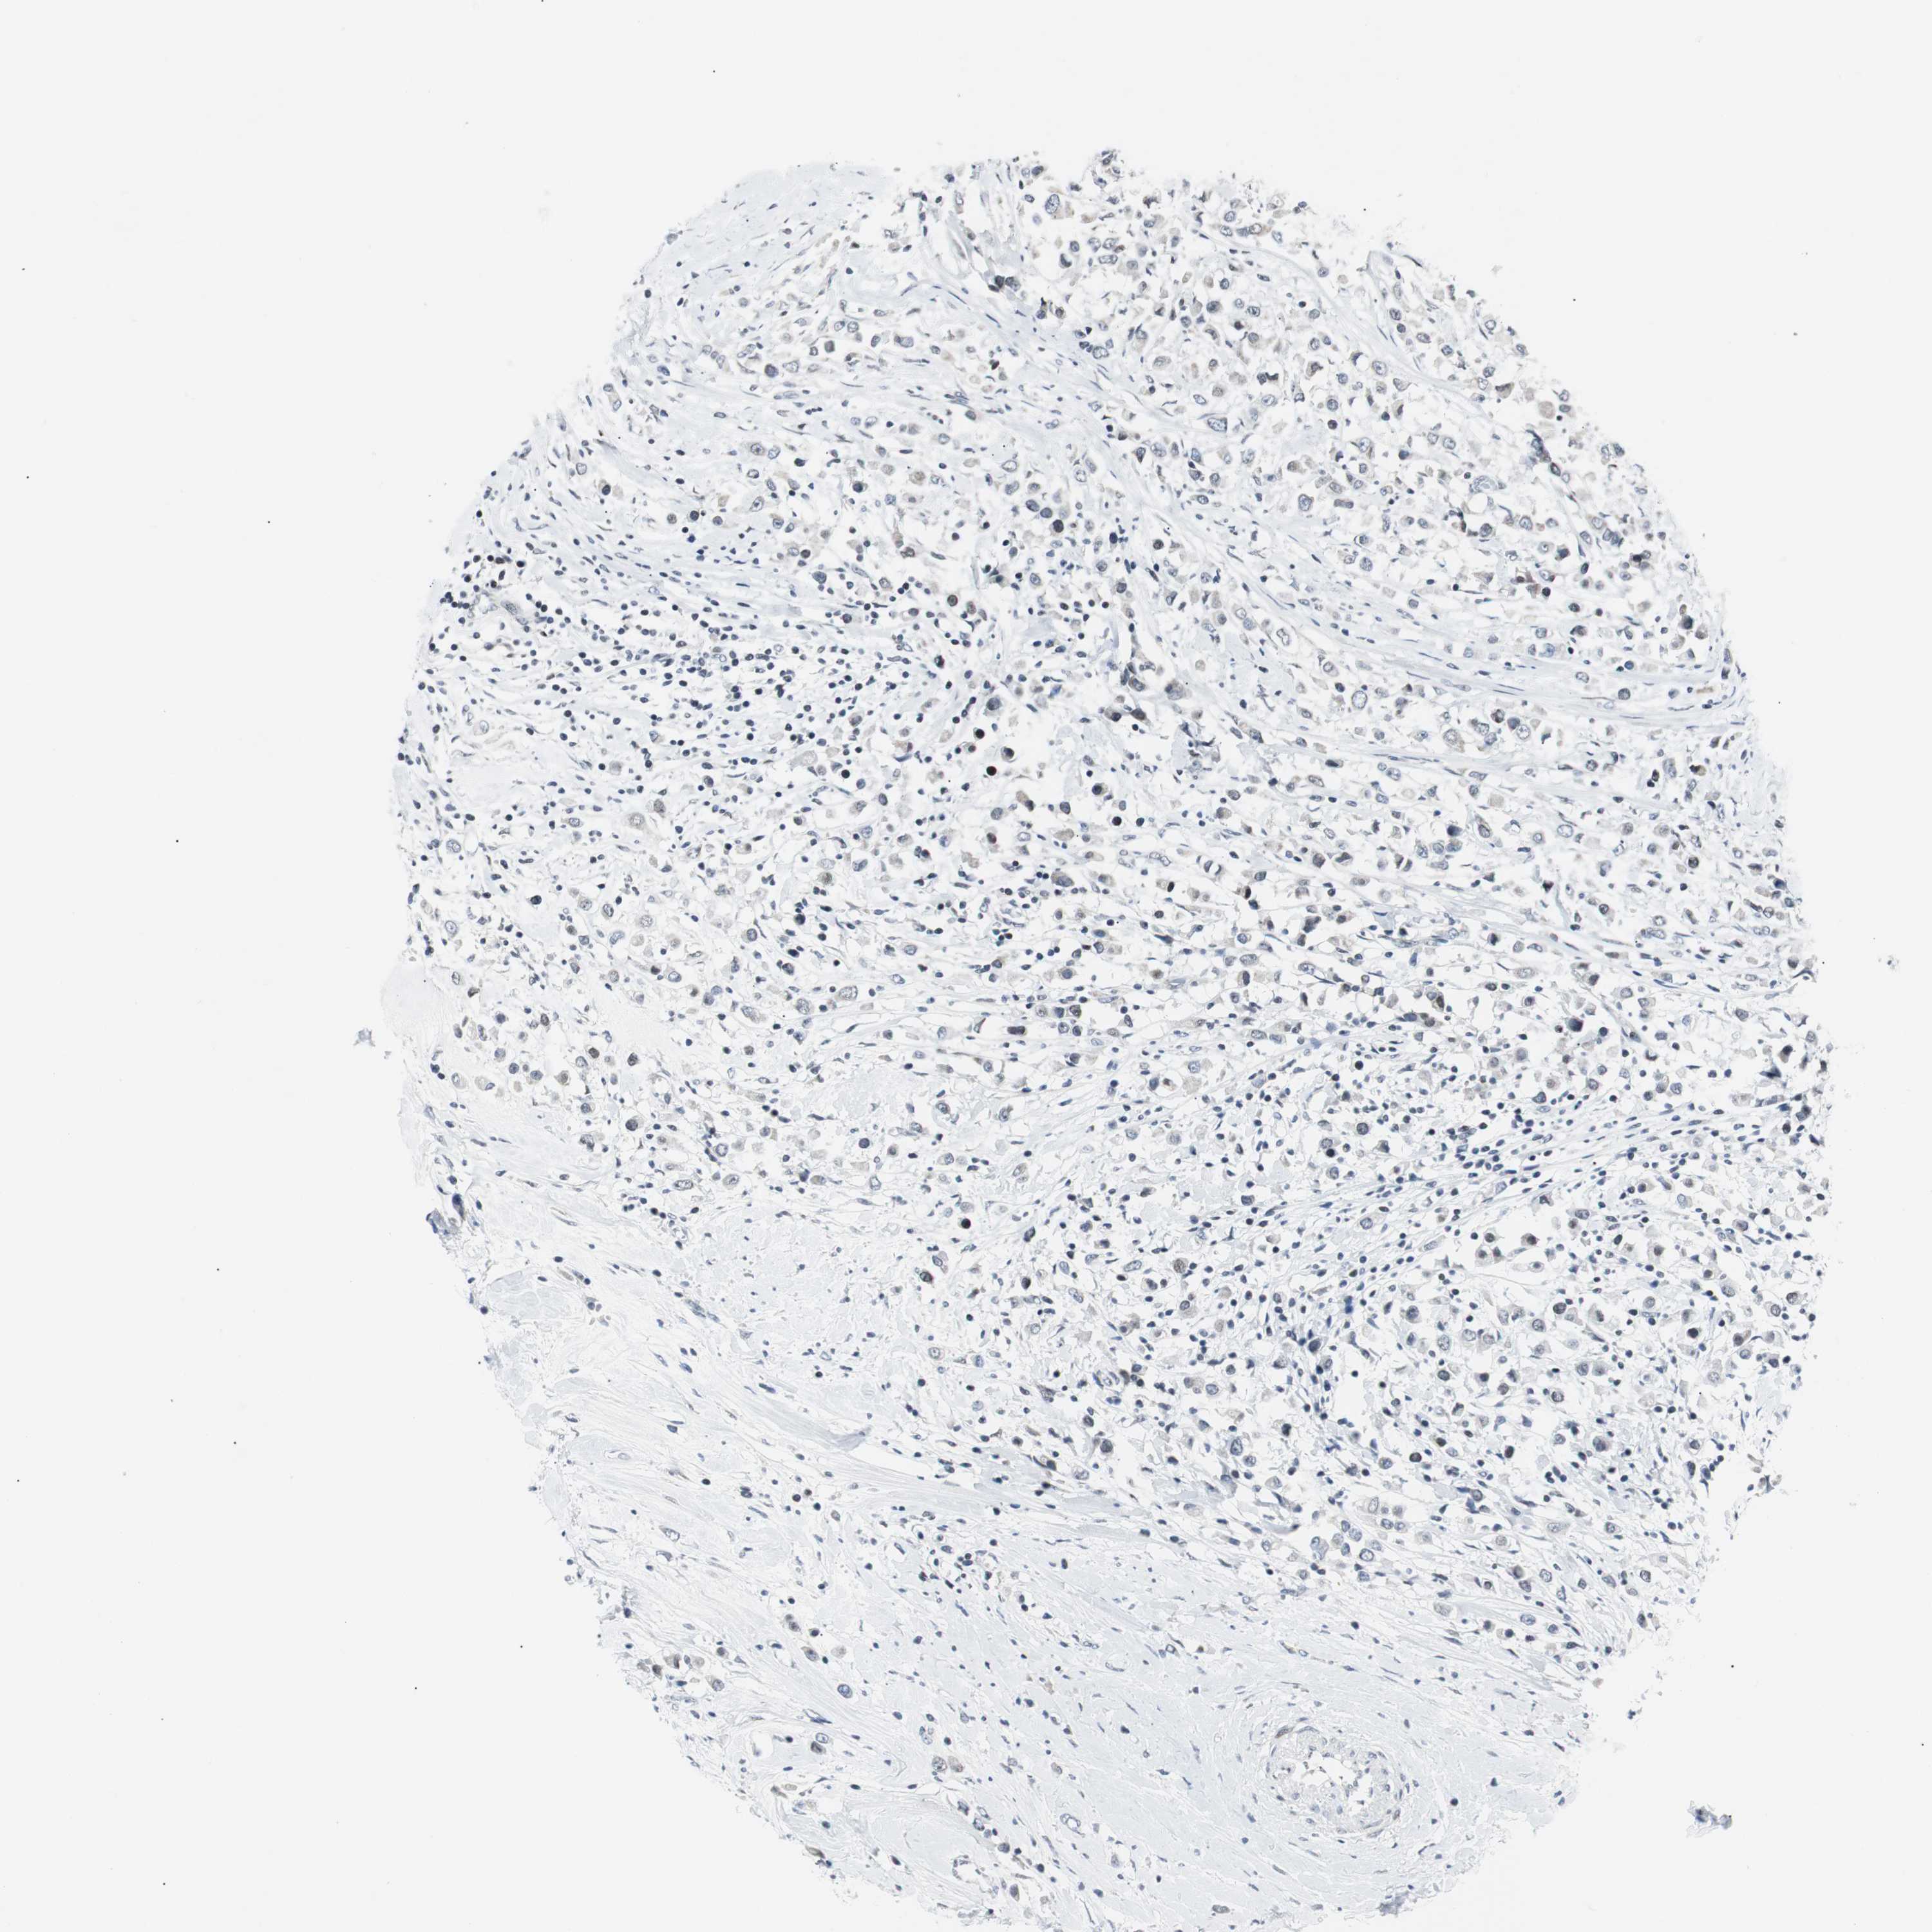

BRCA TCGA BRCA VALIDATION PROTEIN EXPRESSION

ANTIBODIES

AND

VALIDATION